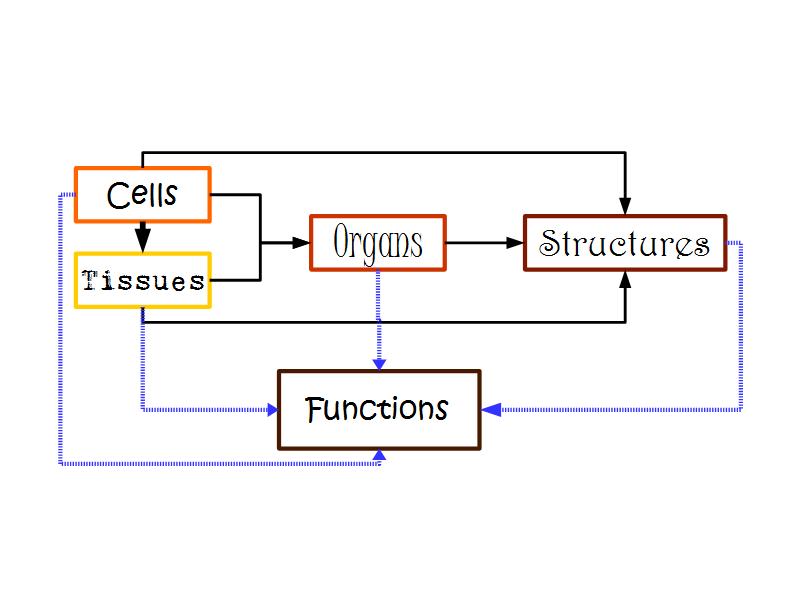

Meta-learning